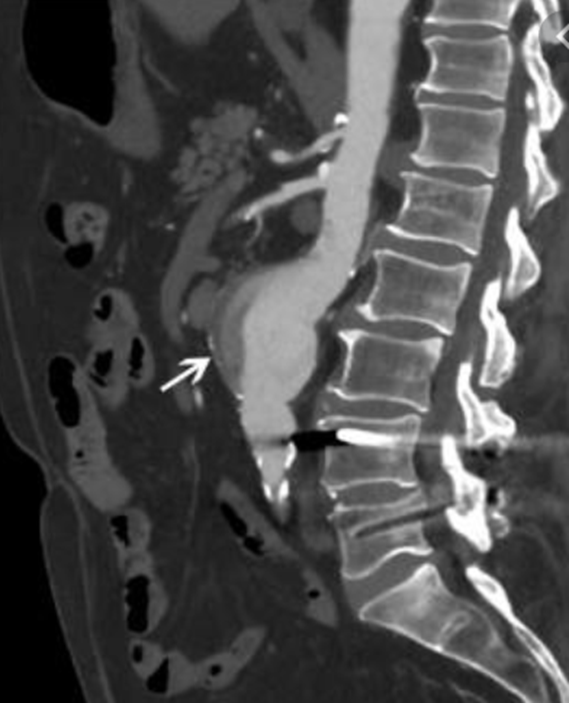

Les anévrismes de l’aorte abdominale (AAA) sont une dilatation excessive et pathologique de l’aorte dont le principal risque est la rupture. Le diamètre normal d’une aorte abdominale se situe entre 15 mm et 25 mm suivant le sexe et l’âge du patient.

bituellement, les patients porteurs d’un anévrisme ne présentent aucun symptôme. Cet AAA est découvert le plus souvent de manière fortuite lors d’un examen (échographie, scanner) réalisé pour une autre raison médicale. L’évolution naturelle d’un anévrisme est sa progression avec une augmentation de taille variable selon les individus. L’anévrisme est soit fusiforme soit sacculaire (en forme de sac). C’est dans l’aorte abdominale en dessous des reins que les anévrismes sont les plus fréquents.

Le meilleur facteur prédictif de rupture connu actuellement est le diamètre maximal de l’anévrisme. Plus l’AAA est volumineux plus il a de risques de se rompre. Cette rupture d’anévrisme peut entraîner jusqu’à 85 % de mortalité. En cas de rupture, 50% des patients toujours en vie lors de leur transfert dans un hôpital décèdent. Ce risque de rupture est faible pour les petits AAA et augmente de manière significative à partir de 55mm de diamètre qui est considéré comme le diamètre à partir duquel l’anévrisme peut ou doit être pris en charge. Au-delà de 55 mm le taux de rupture est de 10% par an et augmente avec la taille pour atteindre 30% pour les AAA supérieurs à 7cm. Dans certaines conditions (anévrisme douloureux, anévrisme sacculaire, anévrisme dans la famille, patients de sexe féminin) les AAA doivent être traités à partir de 50 mm.

La détection ciblée des AAA est recommandée chez les hommes de 65 à 75 ans fumeurs. L’échographie abdominale est l’examen de choix. Lorsqu’un AAA est détecté et que sa taille est importante, l’examen le plus utile pour bien analyser la morphologie de l’anévrisme aortique est un scanner abdominal avec injection de produit de contraste (angio-scanner). Cet examen permet de bien voir les autres artères et en particulier de mesurer la distance qui existe entre les artères rénales et l’anévrisme.

Lorsque le diagnostic d’AAA de taille significative est avéré et que l’état général du patient est satisfaisant, une intervention chirurgicale doit être proposée. Dans 60% des cas, un traitement endovasculaire est réalisable. Ce traitement endovasculaire consiste à exclure l’AAA par une endoprothèse qui est introduite par les artères fémorales au travers de la peau ou via une très courte incision aux plis de l’aine. Cette endoprothèse est un tube bifurqué synthétique renforcé par des mailles métalliques (stents). L’endoprothèse est initialement repliée dans une gaine qui est positionnée correctement au niveau de l’aorte sous contrôle radioscopique (rayons X). Cette endoprothèse est ensuite libérée de sa gaine et déployée jusqu’au niveau des artères iliaques par une manipulation à l’extérieur du patient.

Ce traitement endovasculaire s’est imposé comme le traitement de référence y compris pour les patients en bon état général. La pose d’une endoprothèse peut être réalisée sous anesthésie loco-régionale ou sous anesthésie locale associée à une sédation. L’hospitalisation peut être de très courte durée n’excédant pas, sauf exception, deux ou trois jours. Un contrôle par scanner est nécessaire à la sortie de l’hôpital ainsi que chaque année afin de s’assurer de la bonne position de l’endoprothèse et de l’arrêt de la croissance de l’AAA. Cet examen permet aussi de voir s’il n’existe pas de fuite au pourtour ou à proximité de l’endoprothèse (on parle d’endofuite).